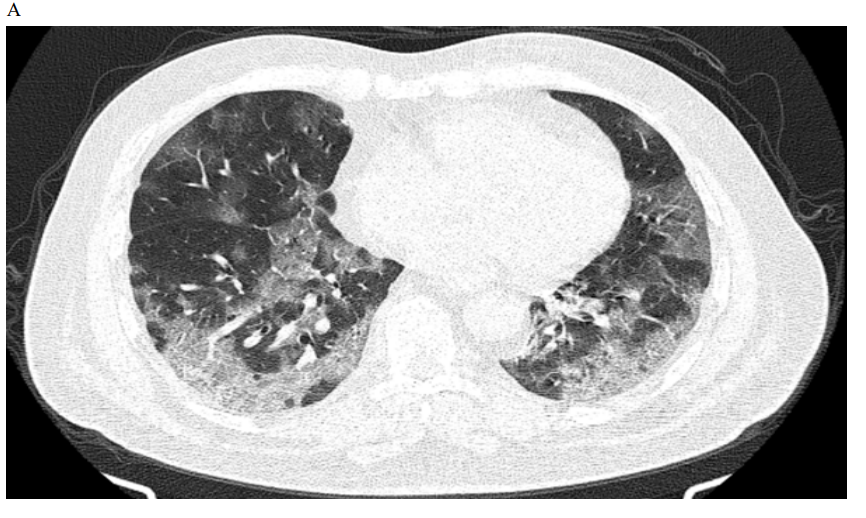

Figure 1: Male patient in favipiravir group shows (A) bilateral lung infiltration with areas of ground glass opacities and peripheral pleural based consolidation, Covid severity score 12, Corad 5. (B) After 3 months of therapy, Improvement of bilateral pulmonary infiltrates with residual basal ground glass opacities, Covid severity score 5.